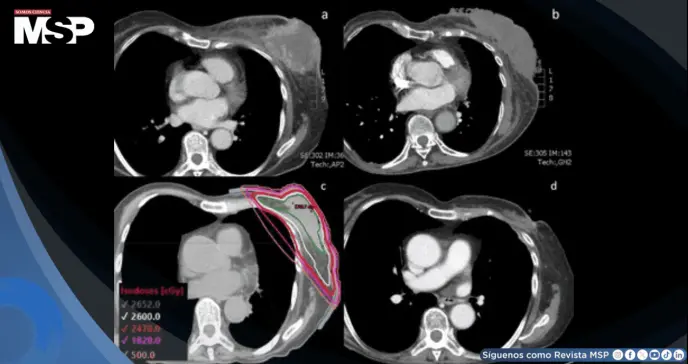

La tomografía computarizada de tórax documentó la gran masa fungiante en mama izquierda, adenopatías axilares y retropectorales con captación anormal, además de múltiples nódulos pulmonares inespecíficos.

La tomografía de control tras tres ciclos de doxorrubicina mostró aumento del tamaño de la masa mamaria y de los nódulos pulmonares, documentando nueva progresión de la enfermedad.

El plan tridimensional conformado cubrió toda la mama desde el borde inferior de la clavícula hasta 2 cm por debajo del surco inframamario, desde el esternón medio medialmente hasta la línea axilar media lateralmente.

Se emplearon campos tangenciales con bloques de media viga, energía de 6 MV y bolo de 5 mm sobre la piel. Los parámetros dosimétricos cumplieron con las restricciones del protocolo FAST-Forward: V95% de mama izquierda 98,4%, dosis media cardíaca 0,35 Gy, dosis media a arteria coronaria 0,99 Gy, V8 Gy de pulmón izquierdo 8,42%, V12,5 Gy 6,8%, y dosis máxima 104,7% de la dosis prescrita. Se realizó verificación diaria con imágenes ortogonales de kilovoltaje.

La tomografía de tórax realizada 3,5 meses después de completar la radioterapia ultrahipofraccionada demostró una reducción tumoral dramática, con medidas de la masa de 0,8 x 1,8 cm, representando una respuesta clínica mayor.